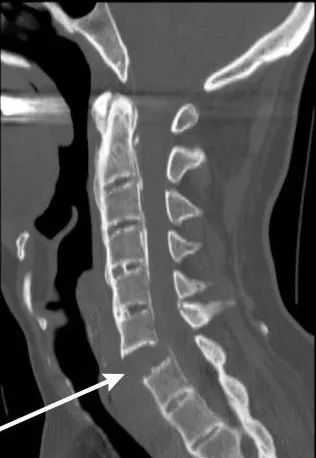

**▲**仰卧起坐對腰椎的壓力比其他運動都大

▲2014年台灣一男子做仰卧起坐

導致頸椎血管爆裂而癱瘓。